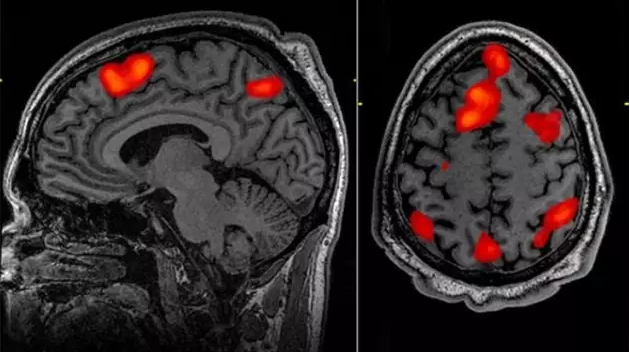

毫不夸张地说,功能性磁共振成像(fMRI)给神经科学领域带来了翻天覆地的变化。当不同脑区的活跃程度发生变化,血流量也会相应改变,神经科学家用核磁共振仪搜集各个脑区血流量变化情况。利用这个技术他们可以非侵入性地找出负责处理不同任务(比如玩经济学博弈游戏,或是阅读文字)的脑区。

fMRI 背后的原理很简单:神经活动需要消耗能量,消耗掉的能量需要补充。这意味着新近活跃的脑区的血流量会增加。高分辨率的 MRI 可以得到这种血流量数据,研究人员借此识别执行某项任务时被激活的脑结构。

然而,这种理论在实际中的应用相当复杂。成像过程将大脑分割成被称为体素的细小三维单位,然后分别记录在每个体素中的活跃度。